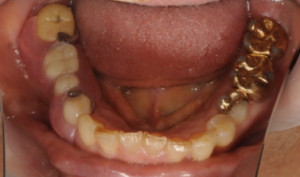

部分入れ歯(ノンクラスプデンチャー)の治療例 2024.06.02 2024.06.13 症状名:右側下顎臼歯部欠損 主訴 歯が無いので噛みにくい 原因 歯が無いことが原因と思われる 診査 型取りをして咬合器上で診査診断 レントゲンにて歯周組織の診断 診断 模型にて、咬合スペースは特に問題ない 噛み合わせのズレはなし 治療方法の選択肢 インプラント治療 ブリッジ 部分義歯(ノンクラスプデンチャー) 部分義歯(テレスコープ義歯) 患者様はノンクラスプデンチャーを選択。 リスク 取り外す必要がある。 クラスプの土台となる歯が、動揺する場合がある 症例写真 治療前 治療後 治療期間 1カ月 費用 165,000円(税込) 結果 審美的にも回復ができ問題なく咀嚼できるようになった。 ご予約・お問い合わせはこちら 浜松町院はこちら 診療時間 10:00 ~ 13:30 / 15:00~19:00休診日:日・祝日 火・木:午前診療のみ月・金:午後診療のみ 03-5422-1291 蒲田院はこちら 診療時間 10:00 ~ 13:30 / 15:00~19:30休診日:土・祝日 水:午後17:00まで日:9:00 ~ 12:00のみ 03-6715-8481 無料相談予約 歯科治療のご相談予約 Webでご予約 翌日以降の日付から Post Share Hatena Pocket RSS feedly Pin it 50代女性の治療例 前の記事 20代女性 前歯の色が気になる 次の記事